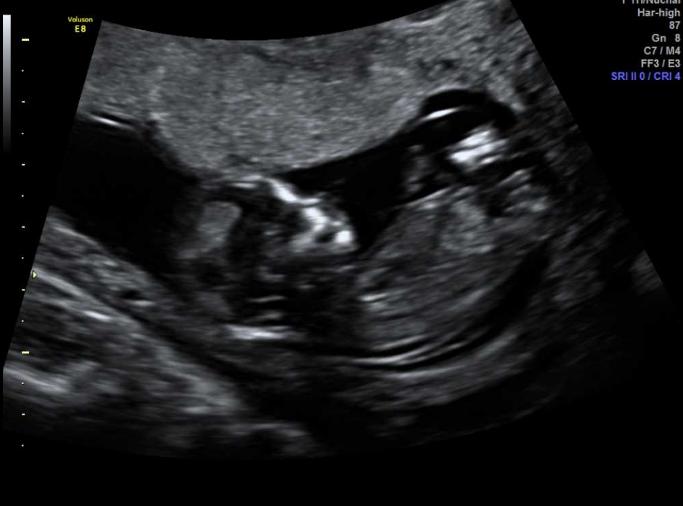

I had my 12 weeks 6 day scan and I'm not sure if i see a nub, any guesses on the gender?

Can you post bigger versions of the pictures? They're really small on my computer so I can't tell what I'm looking at.

WSS!! Too tiny to see! Beautiful baby though pinkinthestars!!